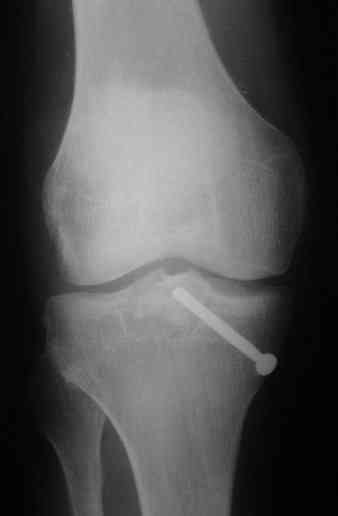

В 3 из 4 случаев мы применили винт, проведенный ретроградно по аналогии с фиксацией заднего края большеберцовой кости при переломах в

области голеностопного сустава. В прищепке рентгенограммы одного из наших пациентов до операции и спустя полгода. Остальные 3 наблюдения

описаны в статье "Изолированный отрывной перелом большеберцовой кости в месте прикрепления задней крестообразной связки // Вестник

травматологии и ортопедии им. Приорова. - 2001. - №1. – С. 38-40. Если есть интерес, могу прислать копию. Ваш случай, безуловно, отличается величиной костного фрагмента, его локализацией, характером и степенью смещения. Но думаю, принцип лечения может быть общим.